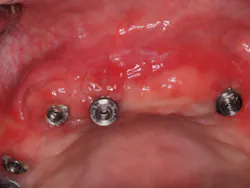

MY COLLEAGUES FREQUENTLY ASK ME what my hygiene follow-up protocol is for full-arch All-on-4fixed bridges (Nobel Biocare; figure 1). There seems to be a wide spectrum as to how clinicians treat patients after their final All-on-4 bridge is delivered, and I am sure that many options exist to adequately manage these patients in the dental hygiene department.

Figure 1: Fixed full-arch bridge